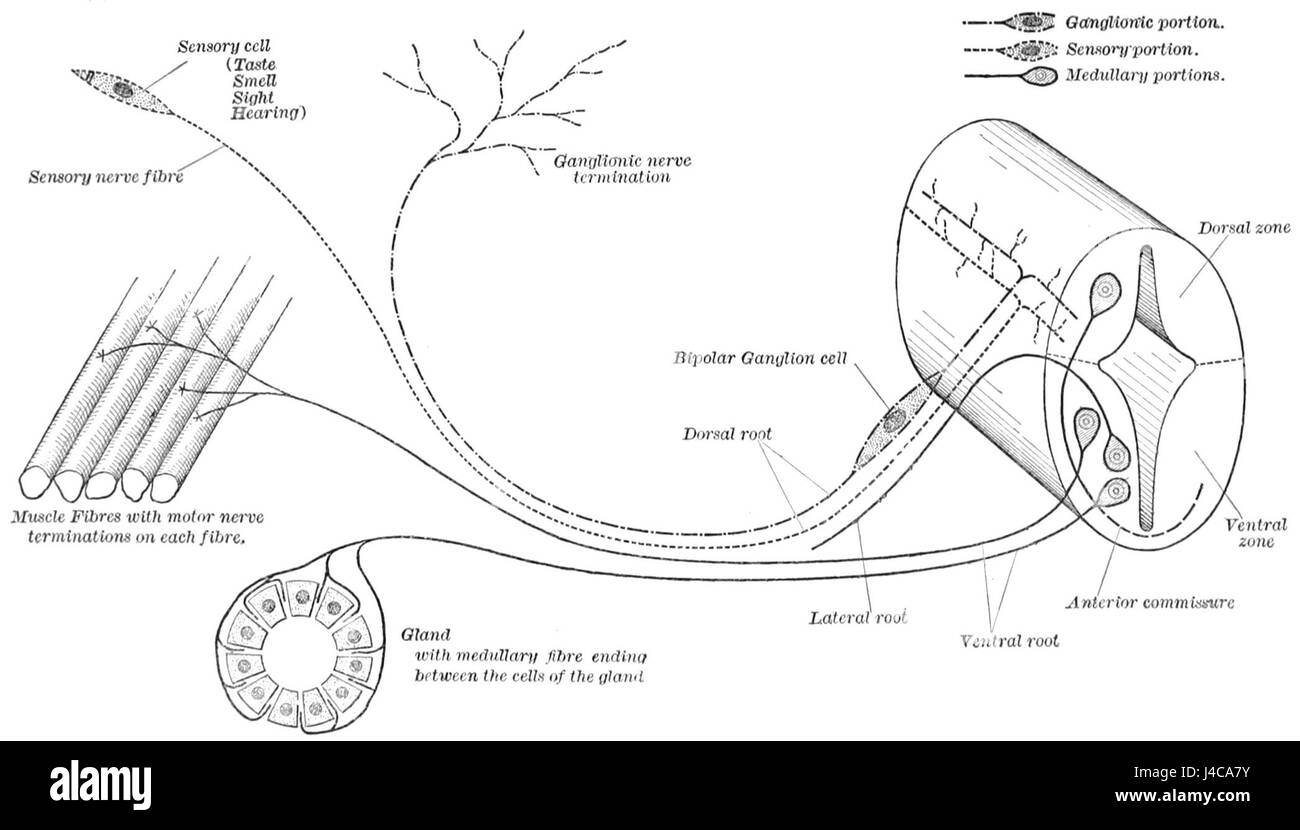

Un diagramme illustrant l'origine et la terminaison des fibres nerveuses, mettant l'accent sur la structure et la fonction du système nerveux dans les études biologiques. Banque D'Imageshttps://www.alamyimages.fr/image-license-details/?v=1https://www.alamyimages.fr/photo-image-un-diagramme-illustrant-l-origine-et-la-terminaison-des-fibres-nerveuses-mettant-l-accent-sur-la-structure-et-la-fonction-du-systeme-nerveux-dans-les-etudes-biologiques-140413055.html

Un diagramme illustrant l'origine et la terminaison des fibres nerveuses, mettant l'accent sur la structure et la fonction du système nerveux dans les études biologiques. Banque D'Imageshttps://www.alamyimages.fr/image-license-details/?v=1https://www.alamyimages.fr/photo-image-un-diagramme-illustrant-l-origine-et-la-terminaison-des-fibres-nerveuses-mettant-l-accent-sur-la-structure-et-la-fonction-du-systeme-nerveux-dans-les-etudes-biologiques-140413055.htmlRMJ4CA7Y–Un diagramme illustrant l'origine et la terminaison des fibres nerveuses, mettant l'accent sur la structure et la fonction du système nerveux dans les études biologiques.